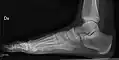

• Foot / Toes - Dorsoplantar, Oblique and Lateral.[19]